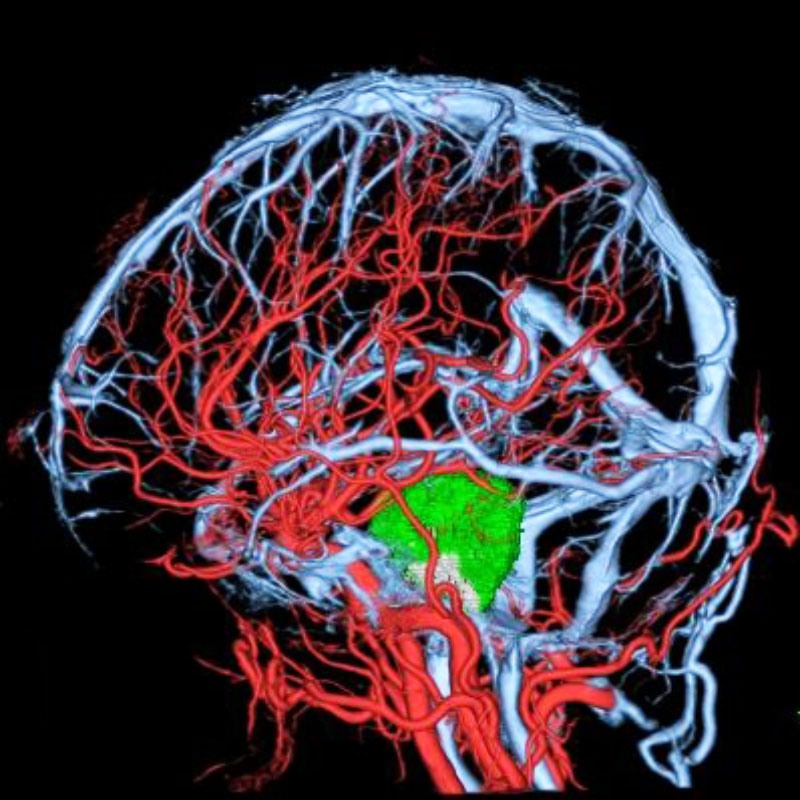

脳動静脈奇形

血管塞栓術

松田/濵田/元永